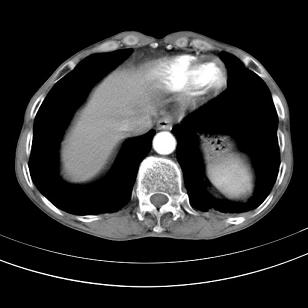

标题: 男,65岁,反复右上腹痛, [打印本页]

标题: 男,65岁,反复右上腹痛,

胃镜提示十二指肠占位